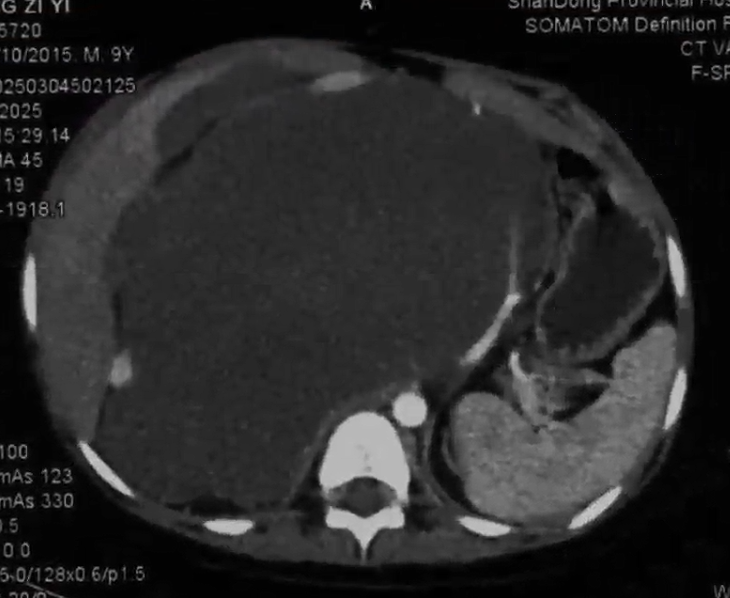

术前腹部增强CT提示腹膜后巨大肿瘤,严重侵犯周围血管及组织器官